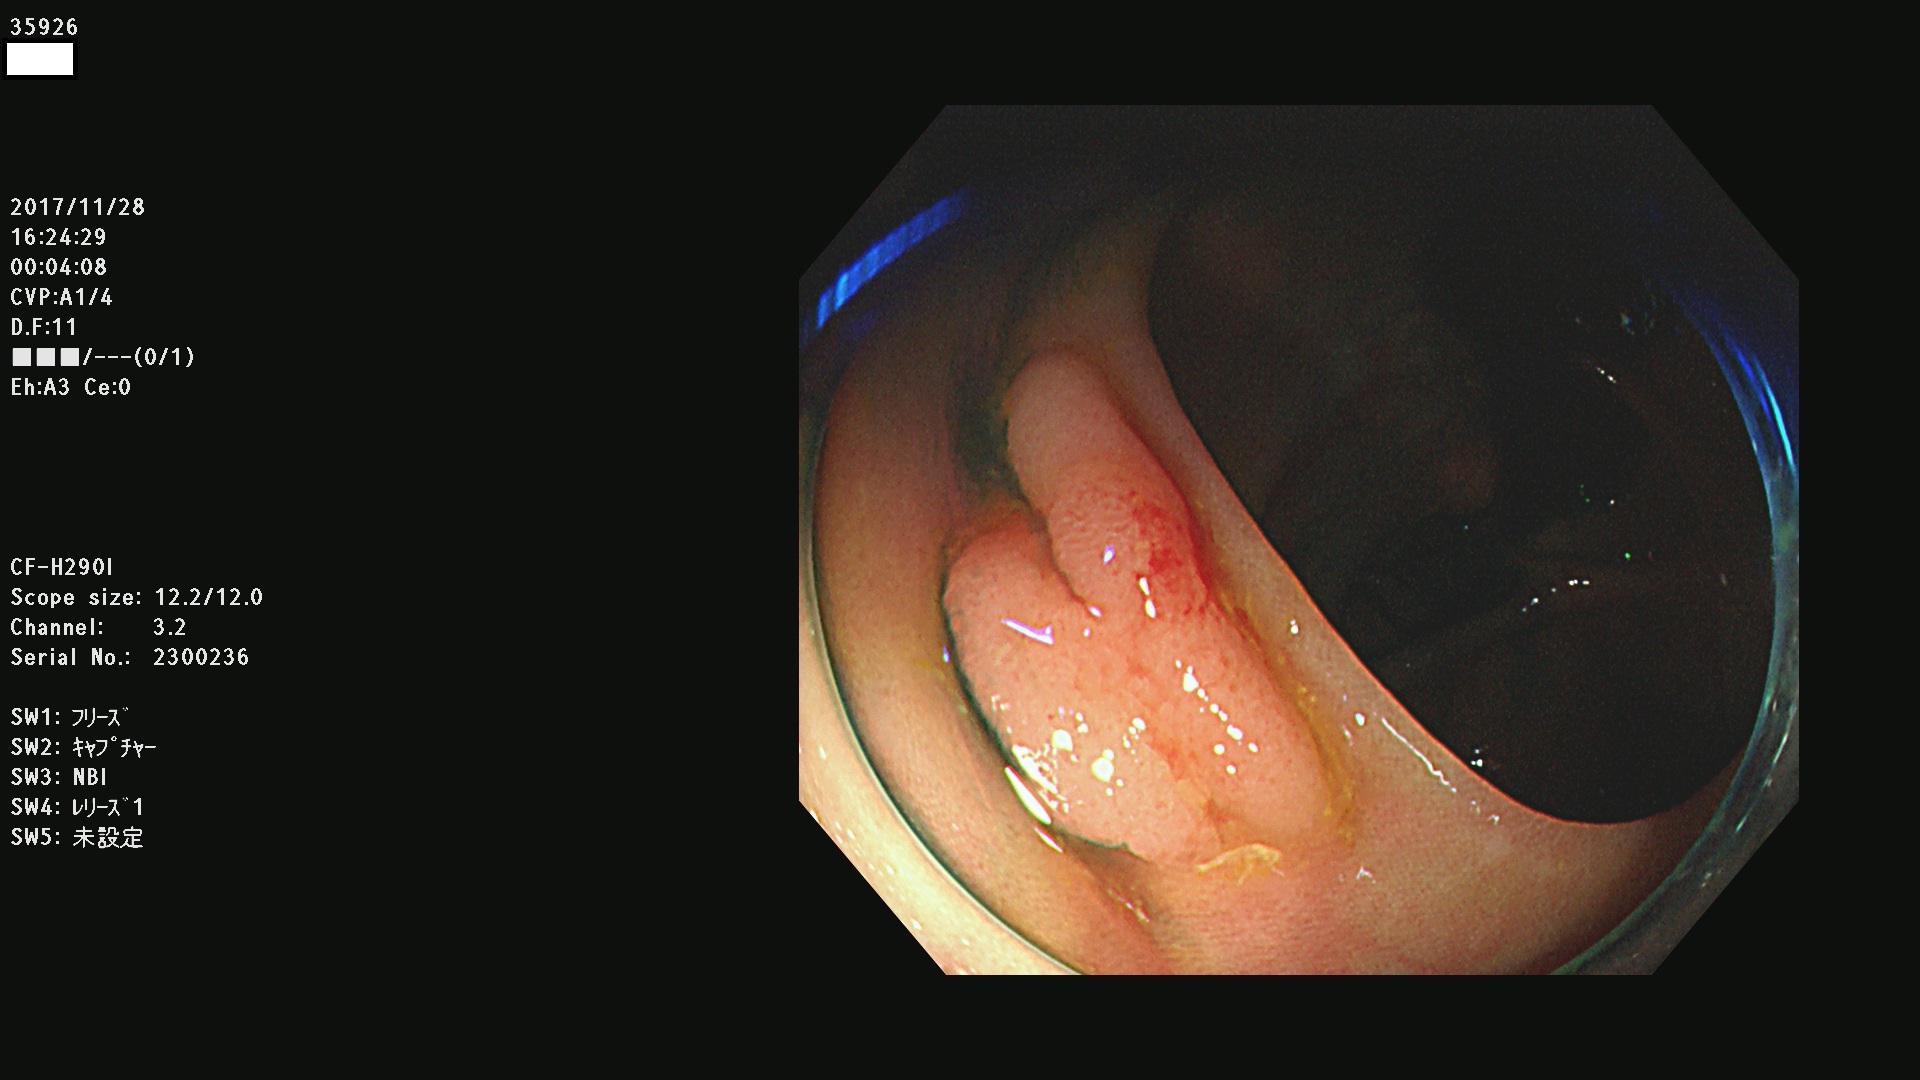

腺腫発見率43 % (カルテ番号 35900〜35999の100名の方の検査結果で集計)大腸癌検診最新情報

以下のカルテ番号の方に腺腫(Adenoma,Group3〜5)が見つかりました(集計法)

35900 35901 35904 35908 35912(SSA/Pのみ) 35914 35918 35922 35925 35926 35928 35931 35932 35933 35934 35937 35939 35943 35945 35947 35949 35951(SSA/Pのみ) 35952 35958 35959 35963 35964(SSA/Pのみ) 35965 35970 35972 35976(SSA/Pのみ) 35977 35978 35979(SSA/Pのみ) 35980(SSA/Pのみ) 35982 35983 35985 35991 35993 35995 35997 35999

発見困難で危険性の高い平坦型病変(上記100名より抽出) ![]()